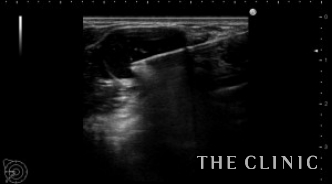

こちらは、多発するヒアルロン酸のしこり治療の症例です。

これまで2回他院でヒアルロン酸豊胸を行っていますが、たくさんのしこりができてしまい当院へ来られました。

両側の皮下、乳腺下、大胸筋内と30個以上のしこりを認めました。

一つ一つエコー下にヒアルロニダーゼを注入して吸引除去しました。

わずかに残存していますが、ほぼしこりは消失しました。

ヒアルロン酸注入によるしこりのエコー診断カルテ